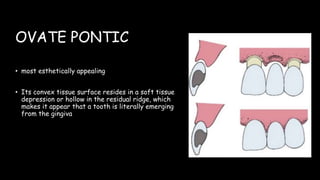

The document discusses pontic design for fixed dental prostheses. It covers pretreatment assessment of residual ridge contours, classifications of ridge deformities, surgical modification techniques, and ideal requirements for pontics. Pontic designs are classified based on their shape and materials. Factors in pontic selection include esthetics and oral hygiene. Common designs for anterior and posterior regions are described, including sanitary, ovate, and saddle pontics. Biological considerations for pontic design involve maintaining the residual ridge, abutment teeth, and supporting tissues.

![PONTIC DESIGN CLASSIFICATION

• According to Rosenstiel

A] MUCOSAL CONTACT:

1. Ridge lap

2. Modified ridge lap

3. Ovate

4. Conical

B) NO MUCOSAL CONTACT

1. Sanitary (hygienic)

2. Modified sanitary (hygienic)](https://image.slidesharecdn.com/ponticandponticdesigns-201011153902/85/Pontic-and-pontic-designs-23-320.jpg)